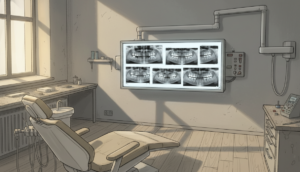

定期的なレントゲン検査

歯根吸収は初期段階では自覚症状がほとんどありません。そのため、定期的なレントゲン検査で歯根の状態をチェックすることが不可欠です。

当院では、治療の進行状況に応じて適切な間隔でレントゲン撮影を行い、歯根吸収の早期発見に努めています。万が一、歯根吸収が確認された場合は、治療を一時的に休止したり、力を弱めたりするなど、適切な対応を行います。